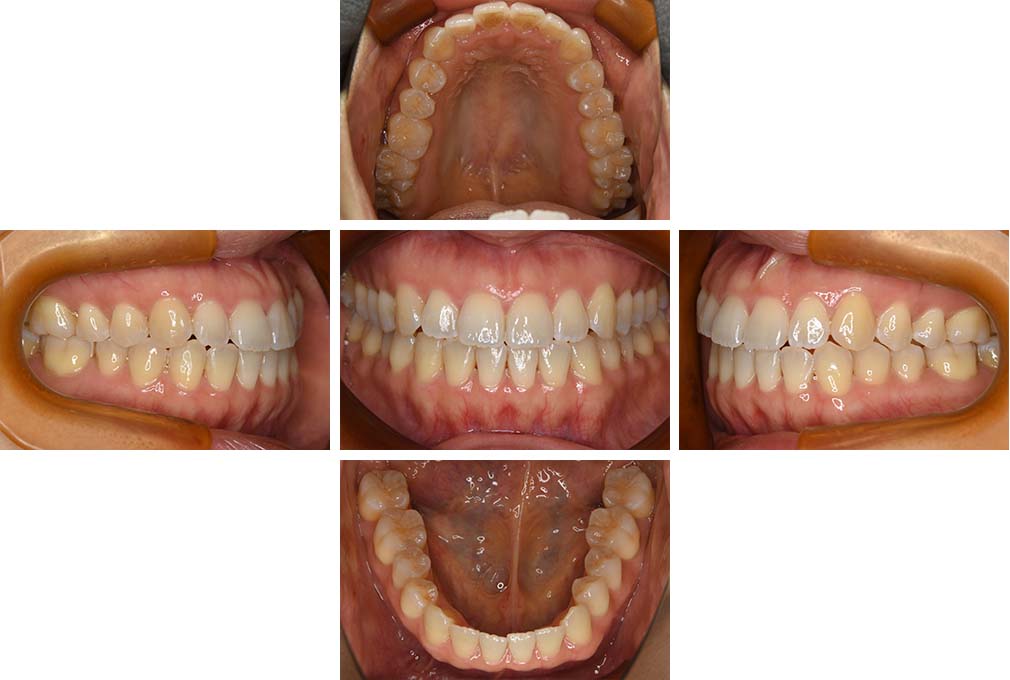

CASE:04

アングルⅢ級傾向を持つ叢生

初診時年齢 22歳

性別 女性

治療費の目安 105万円程度(治療開始時)

上顎右側犬歯が唇側に転位していることを主訴に県内歯科医院から紹介来院された。骨格的にはⅢ級傾向で上顎右側犬歯が唇側転位となり、側切歯が口蓋側に転位していた。下顎前歯が叢生になっていることも相まって上下の正中線は右側に大きくずれていた。アングルⅢ級傾向を持つ上下顎前歯部叢生と診断した。

上下顎小臼歯を抜歯していただき上顎舌側、下顎唇側マルチブラケット装置を使用して動的治療を行った。矯正用ゴムの使用など協力状態も良く、正中線の大きな移動があったのも関わらず2年10カ月で装置を撤去し保定へ移行した。保定移行後14年が経過し、ご息女の診察でご来院いただいていたことから、口腔内を拝見したが、下顎前歯のわずかなずれがあったものの大きな歯列の乱れはなく歯列は安定していた。動的治療期間2年10カ月間。

治療前

22歳6か月

治療後

動的治療期間2年10カ月間

25歳6か月

治療終了

動的治療終了後2年2カ月

28歳8か月

14年経過

動的治療終了後14年7カ月

40歳1か月